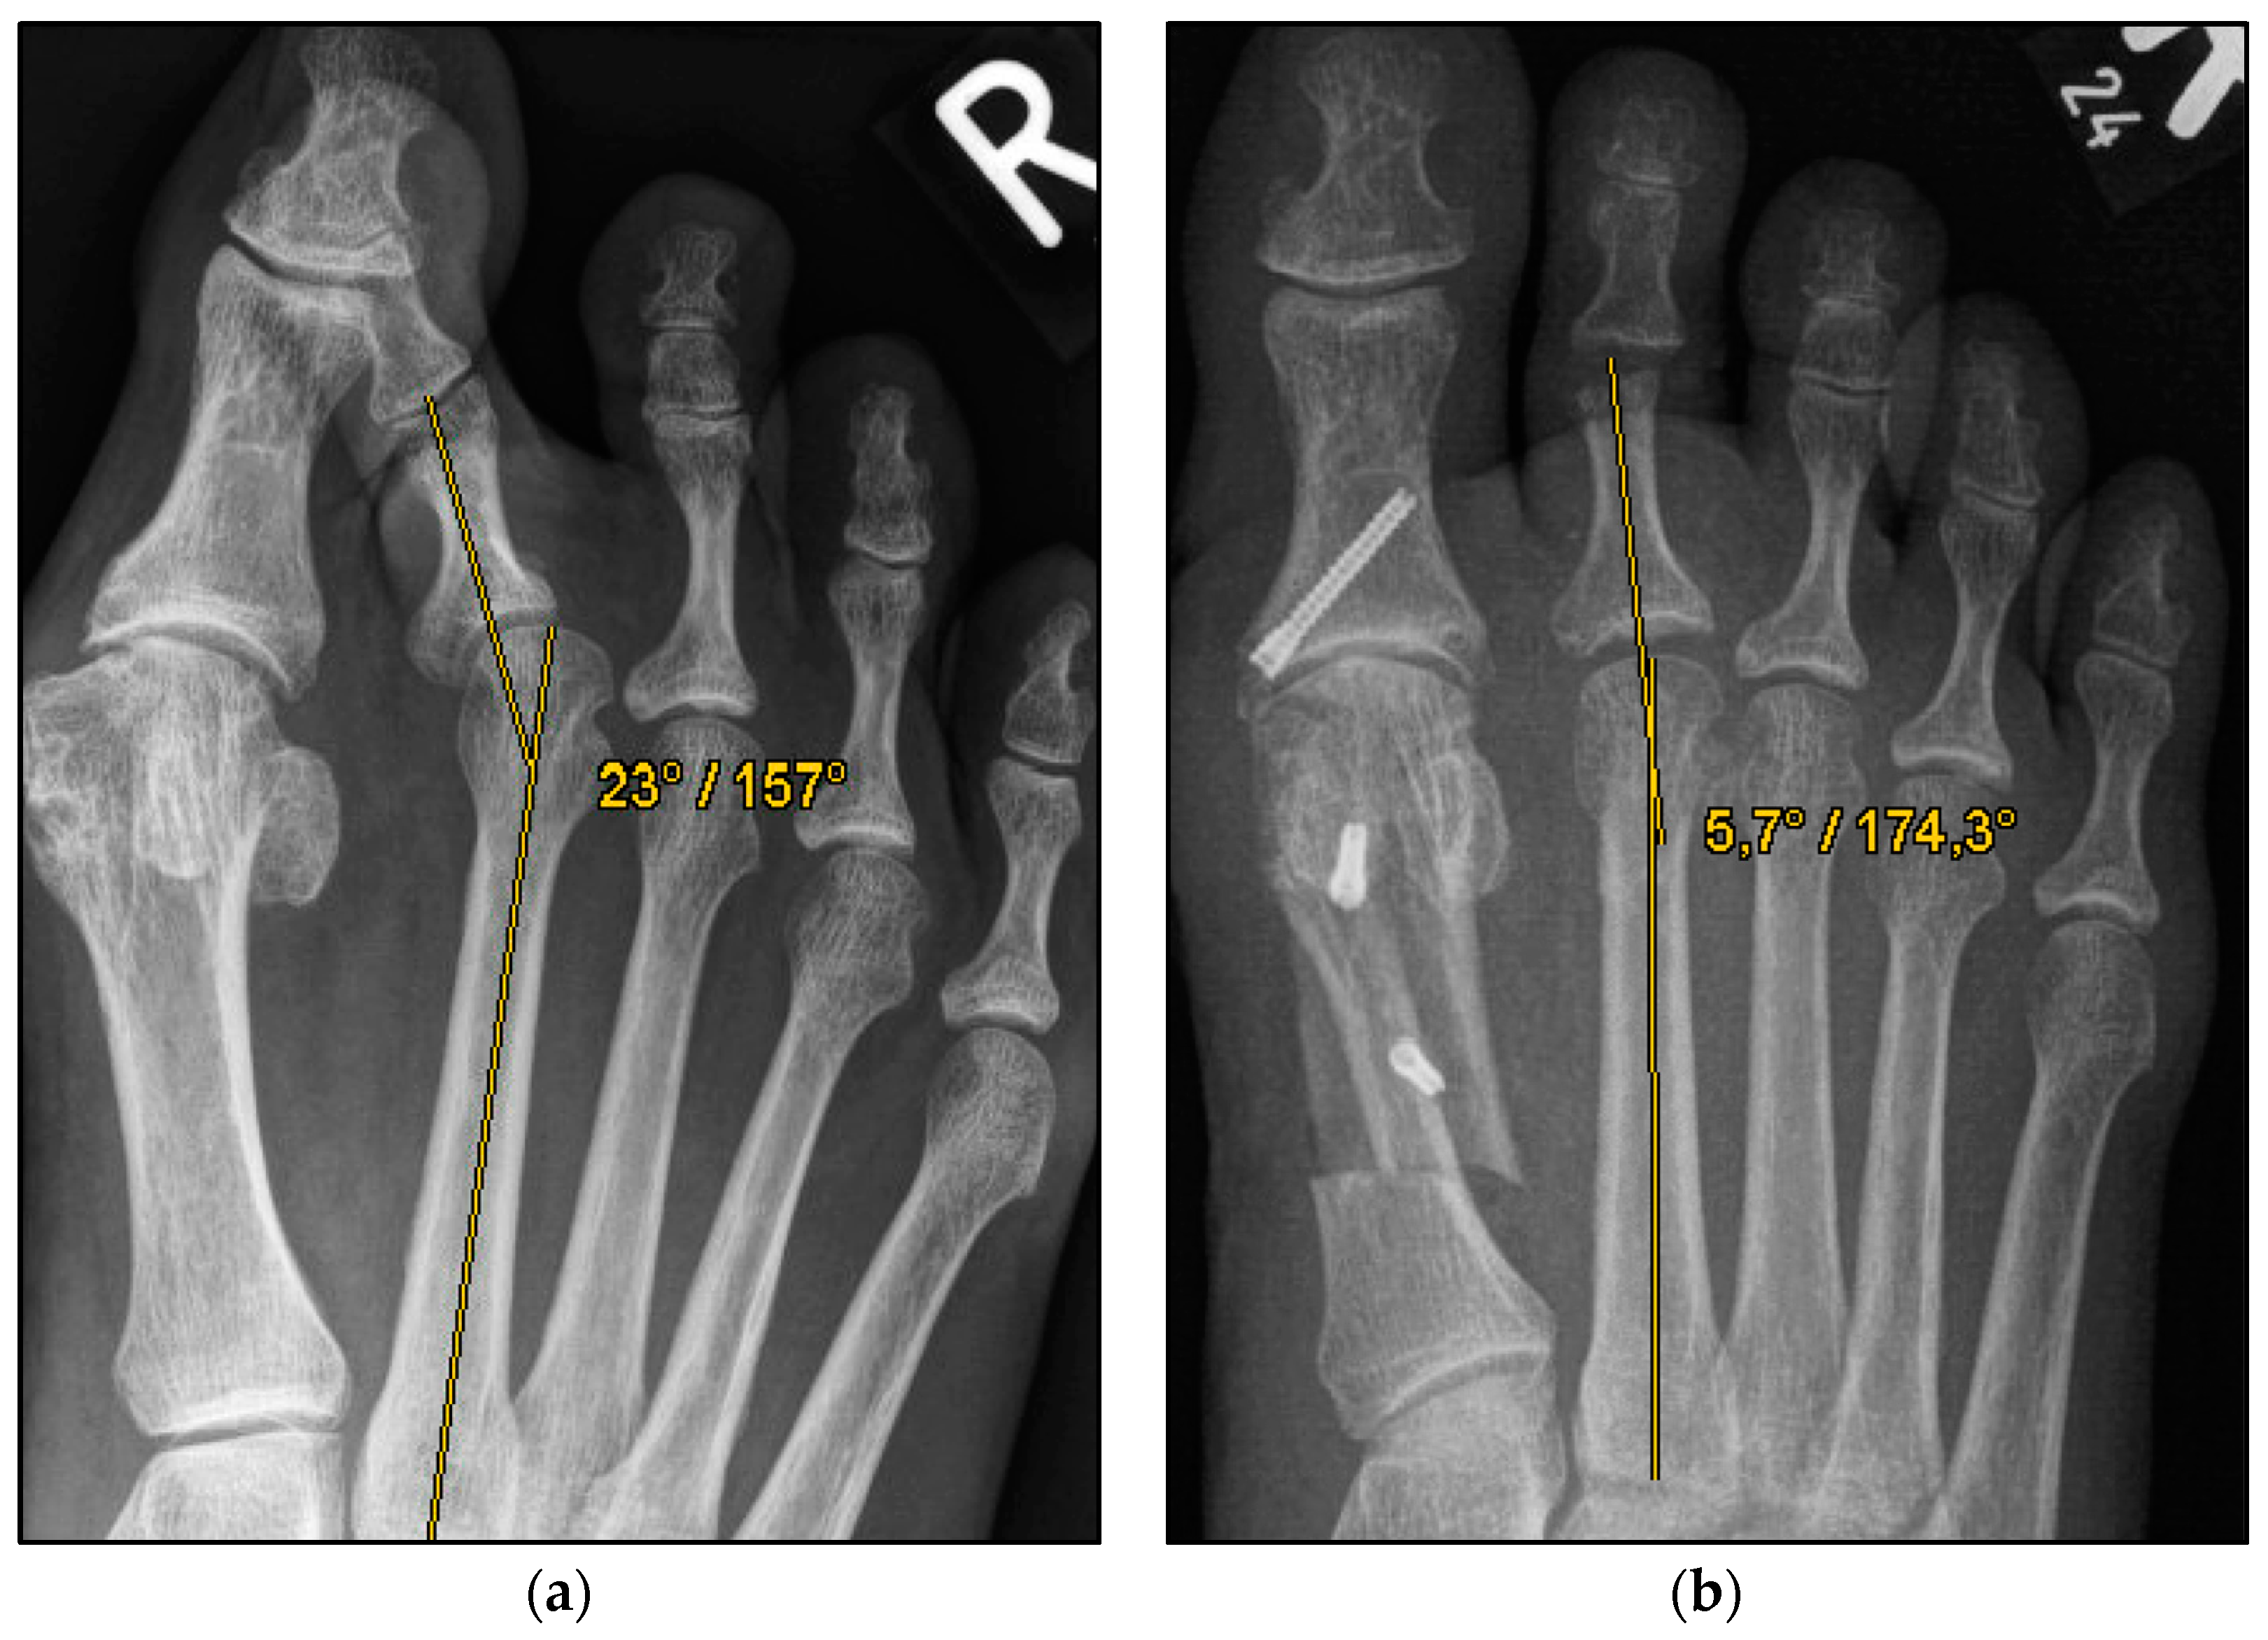

Figure 2.

Pre- and postoperative radiographic results of combined hallux valgus surgery and Weil osteotomy of metatarsal 2 (group B without screw), right foot. (a) Weight-bearing radiograph: anteroposterior view preoperative, (b) weight-bearing radiograph: anteroposterior view, 2 months postoperative.